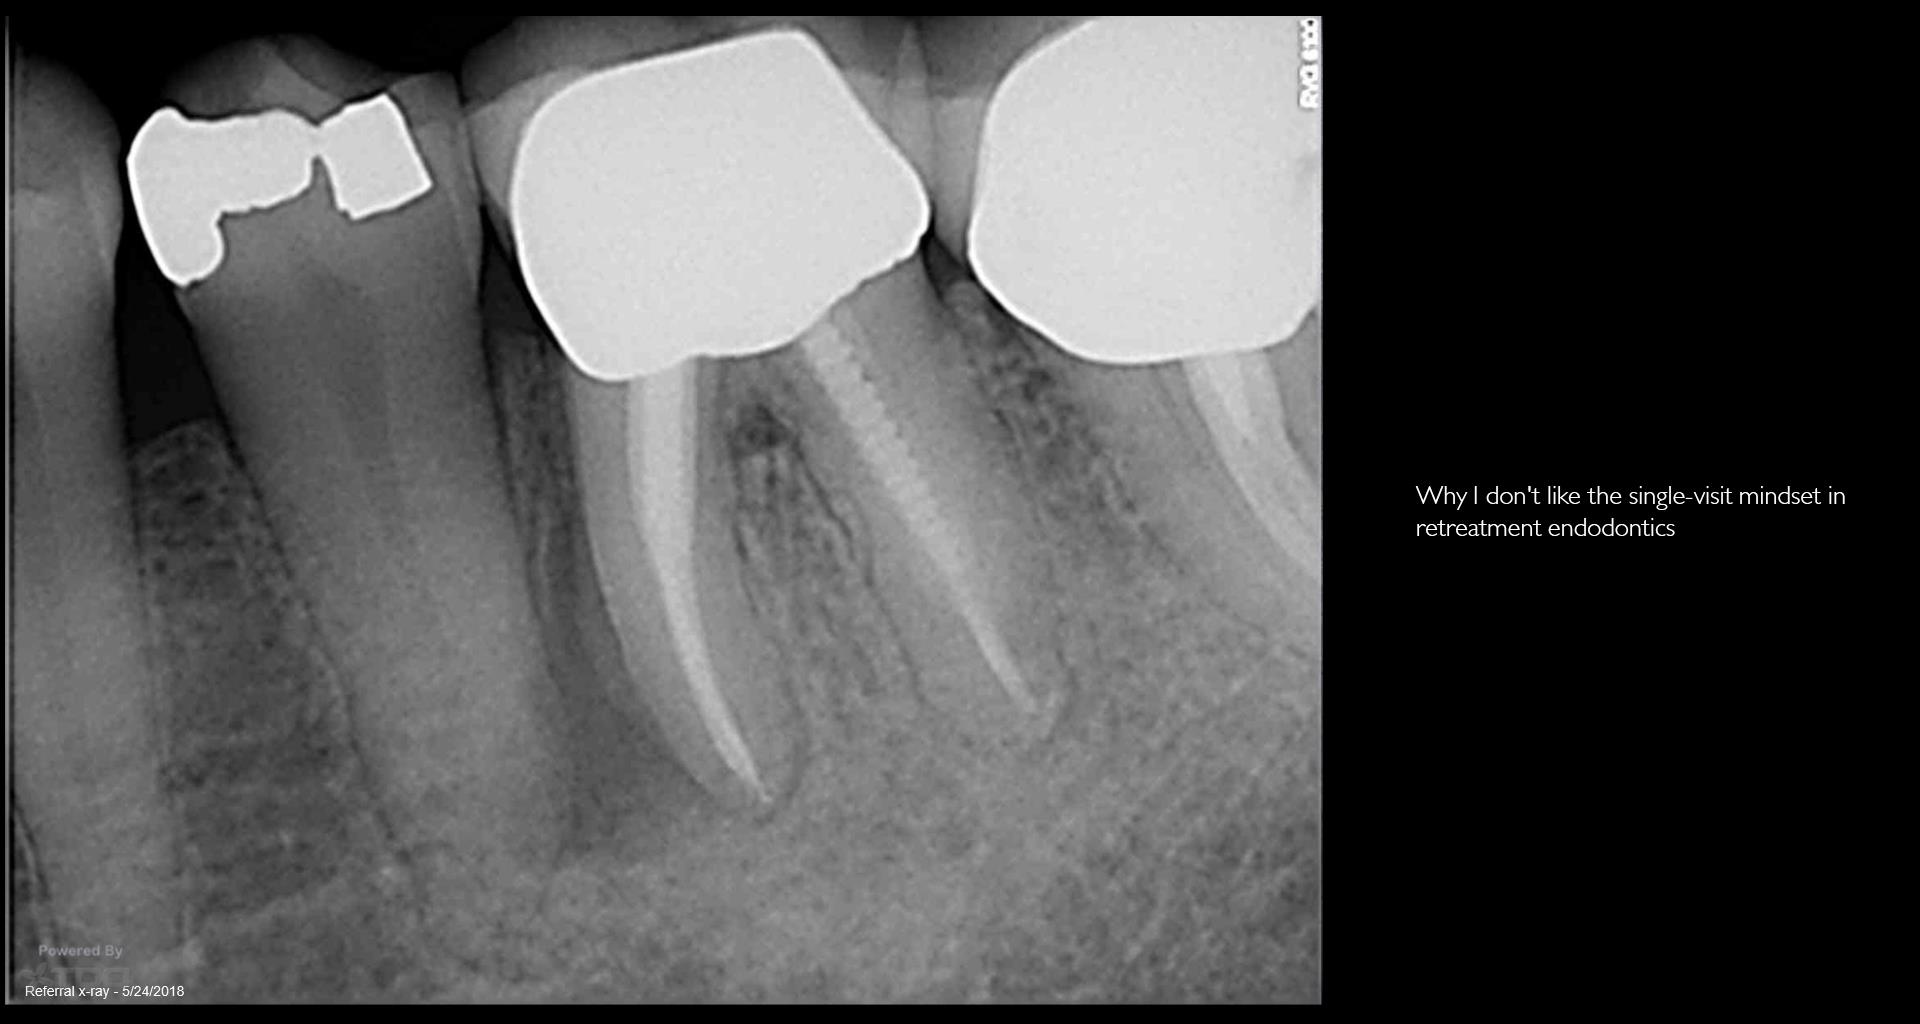

Patient in for a sinus tract check recall today asking questions…… All treatment done by endodontists. Always done in a single visit. The 2nd endodontist told the patient she was “cured”. He never checked her again. When she called and said she may have a problem… they told her it wasn’t necessary. Her GP told her to have it extracted. Is it fractured? Is it a failing RCT that can be saved? How does one tell? To me, to do a retreatment like this in a single visit….. Well…it isn’t the way I would like to be treated. Because you end up with cases like this. By the way: no symptoms. gbc